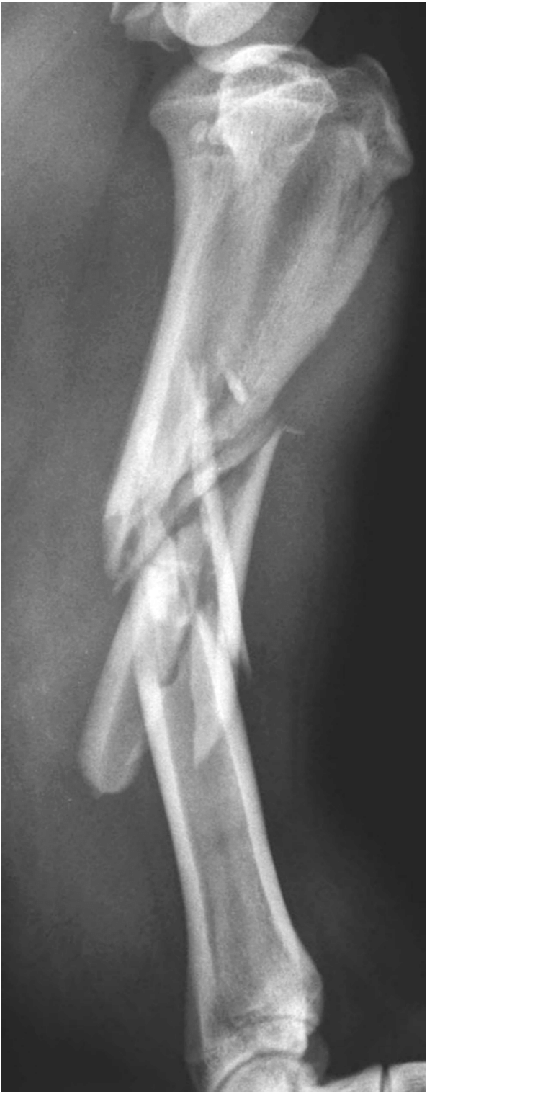

What type of fracture is this and what view is the x-ray?

Comminuted fracture (of the tibial shaft)

Lateral view